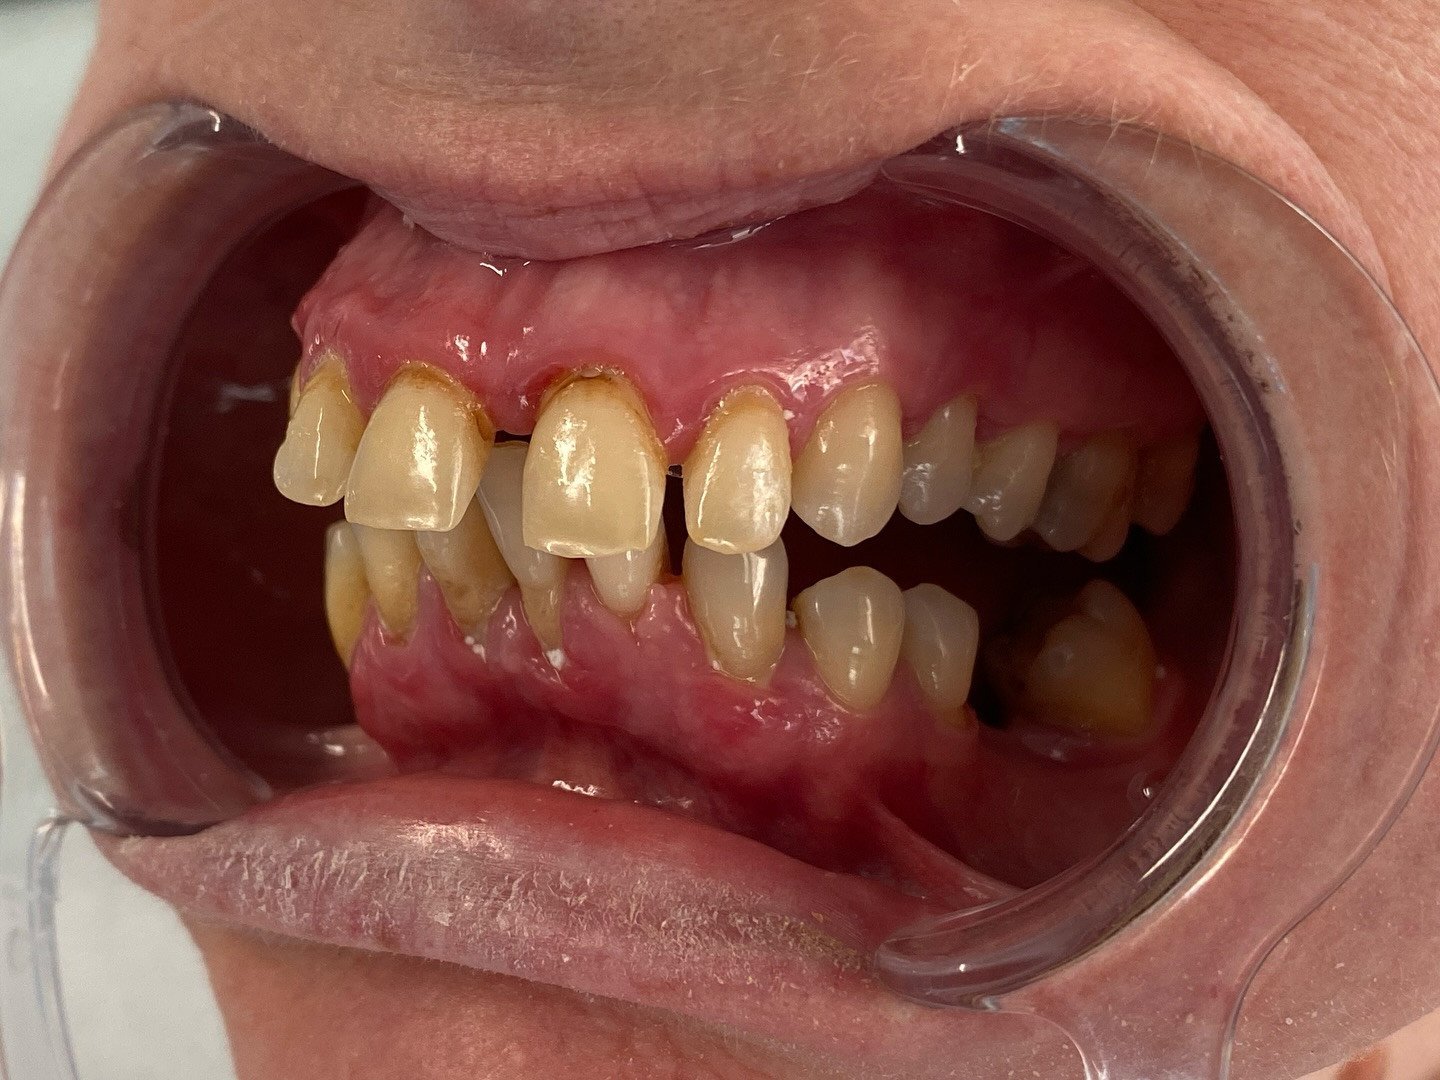

Rehabilitimi i të dy nofullave me kurora nga metal-porcelani

Rehabilitimi i të dy nofullave me kurora nga metal-porcelani duke kthyer funksionin dhe estetikën e dëshiruar.